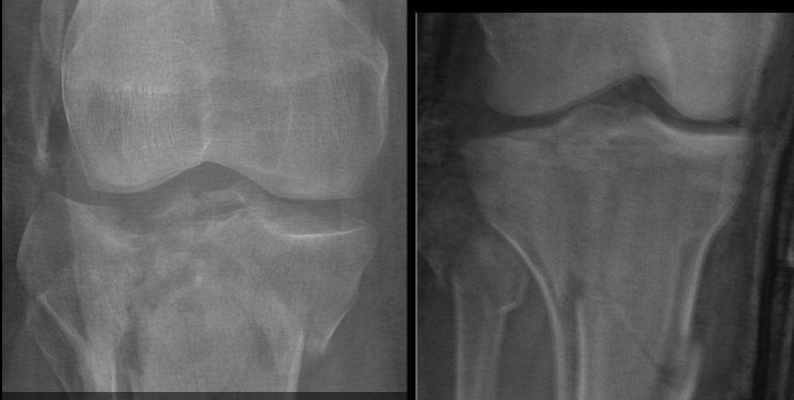

21

Q

A

Shatzker 5 y 6